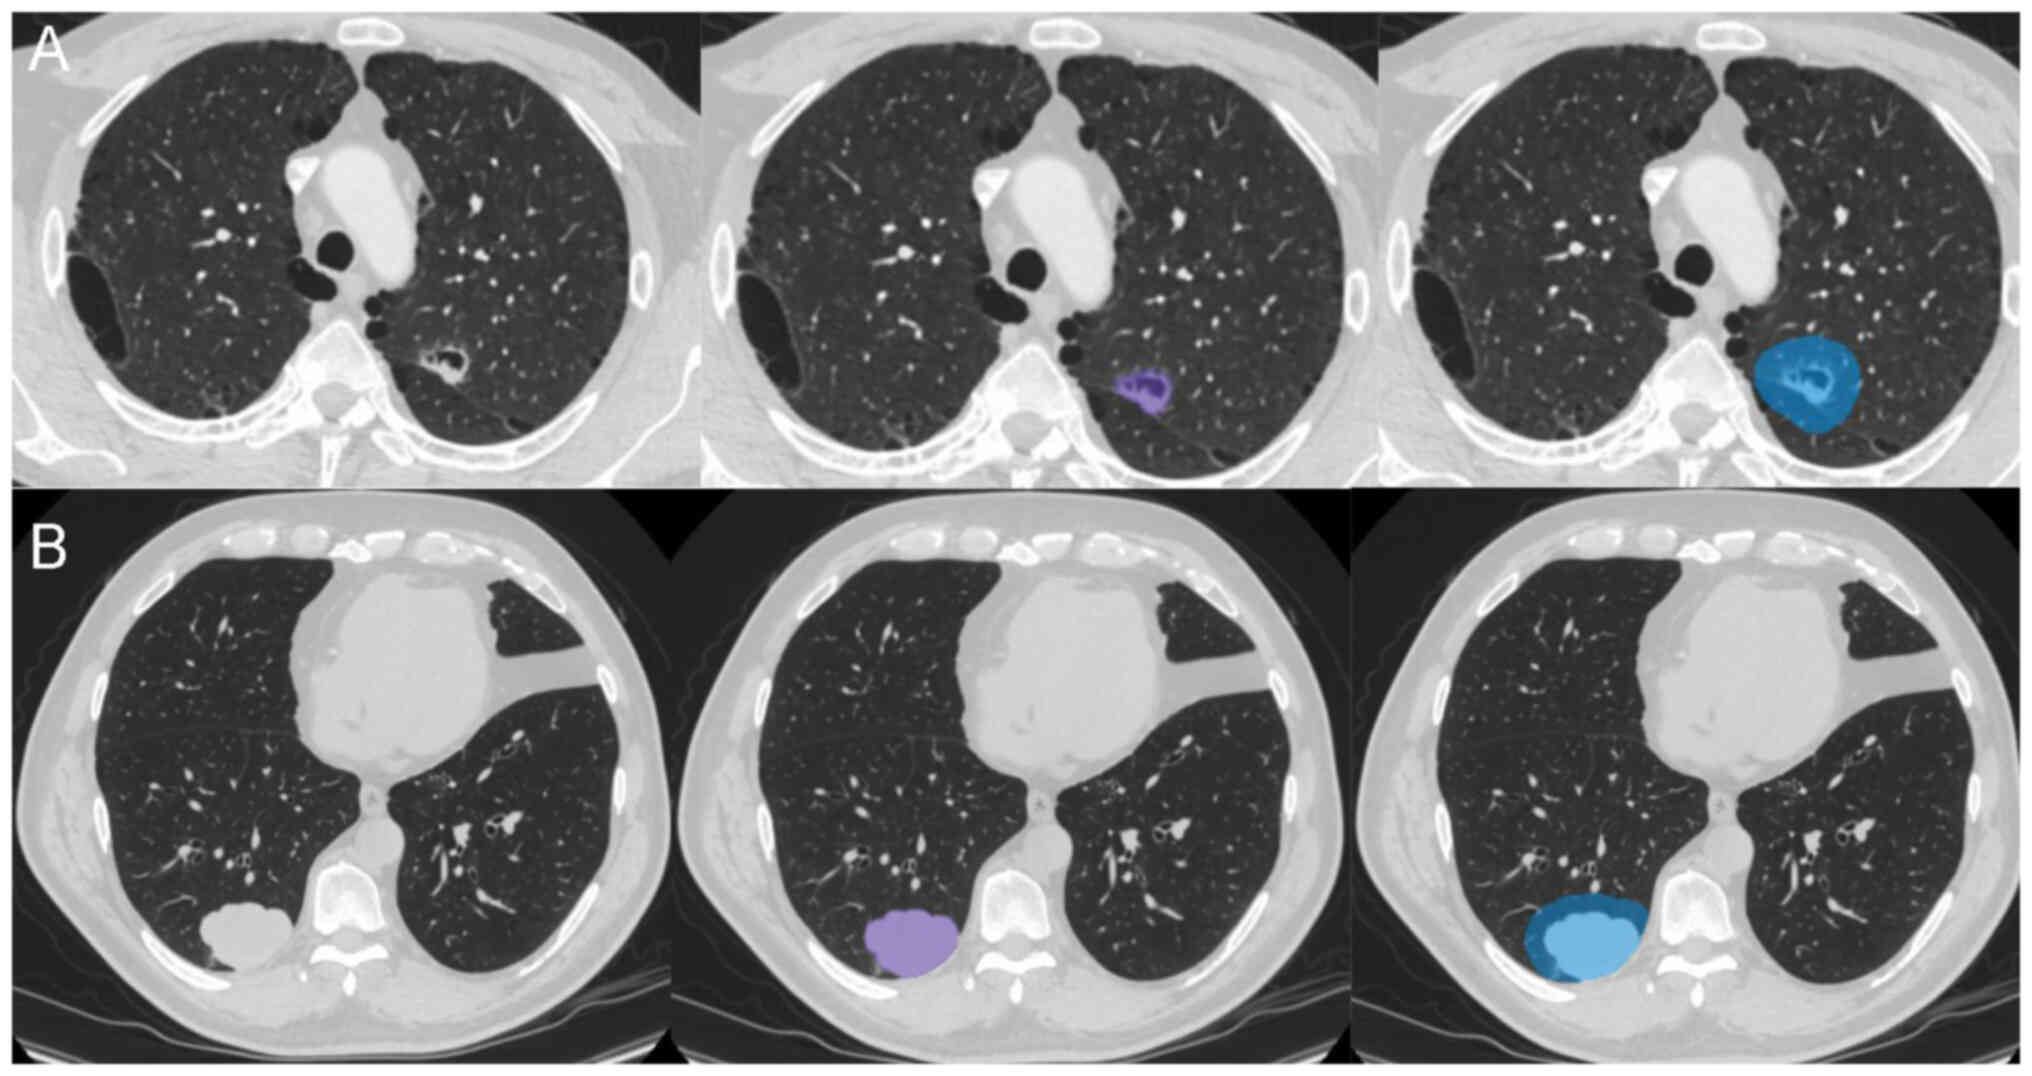

Image segmentation

To eliminate differences in voxel size between different datasets, images were resampled to 1×1×1 mm3 using RIASEG software (28,29) (https://github.com/lisherlock/RIASEG; version 1.0). In the present study, semi-automatic segmentation was employed to delineate the VOI. After the software automatically segmented the intratumoral region layer by layer, a junior radiologist (radiologist A; 3 years of experience) checked and adjusted the segmented areas. The final segmentation was evaluated again by a senior radiologist (radiologist B; 10 years of experience) for quality control. Following the segmentation of the intratumoral region VOI, the built-in extension function software of the was used to automatically expand the outlined VOI outward by 10 mm (21) to create a VOI that included the peritumoral region, thus generating the intratumoral and peritumoral regions VOI (Fig. 2). During the segmentation process, attention was paid to exclude large blood vessels, bronchi, soft tissues of the chest wall, ribs and mediastinum to ensure that the VOI reflected the actual lesion. Both the intratumoral and the combined intratumoral and peritumoral VOIs were mapped for each lesion.

Image segmentation. Representative

images from (A) Patient 1 and (B) patient 2 in the present study.

Purple represents the intratumoral region, and blue represent the

intratumoral and peritumoral regions.

Figure 2.

Image segmentation. Representative images from (A) Patient 1 and (B) patient 2 in the present study. Purple represents the intratumoral region, and blue represent the intratumoral and peritumoral regions.